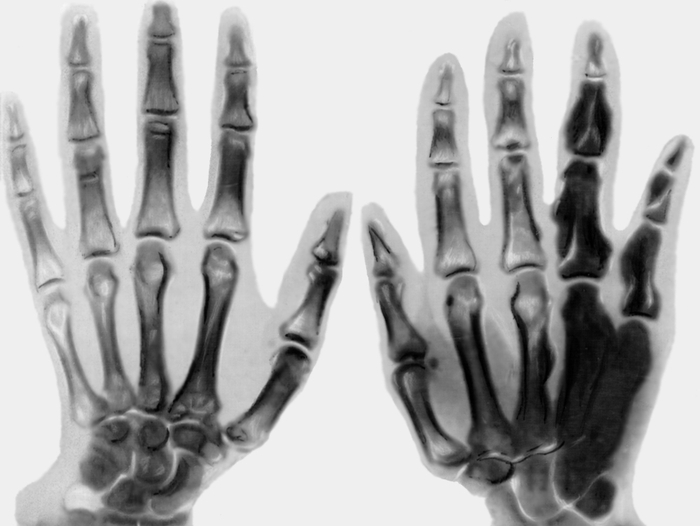

Рентгенологические проявления данного заболевания имеют ярко выраженные особенности. В пораженной области кости наблюдаются участки уплотненной ткани, которые выглядят как продольные линии или остеосклероз. На рентгеновском снимке заметен симптом, напоминающий тающую свечу. Также отмечаются изменения в архитектонике и надкостнице. Костный мозг атрофируется и заменяется соединительной тканью. Утолщение кости наблюдается только с одной стороны.

| Рентгенологическая картина | Характерная “восковая” или “капельная” склеротическая гиперденсификация костей, напоминающая капающую свечу. Асимметричное поражение. | Нет специфического лечения, направленного на регресс изменений в костях. |